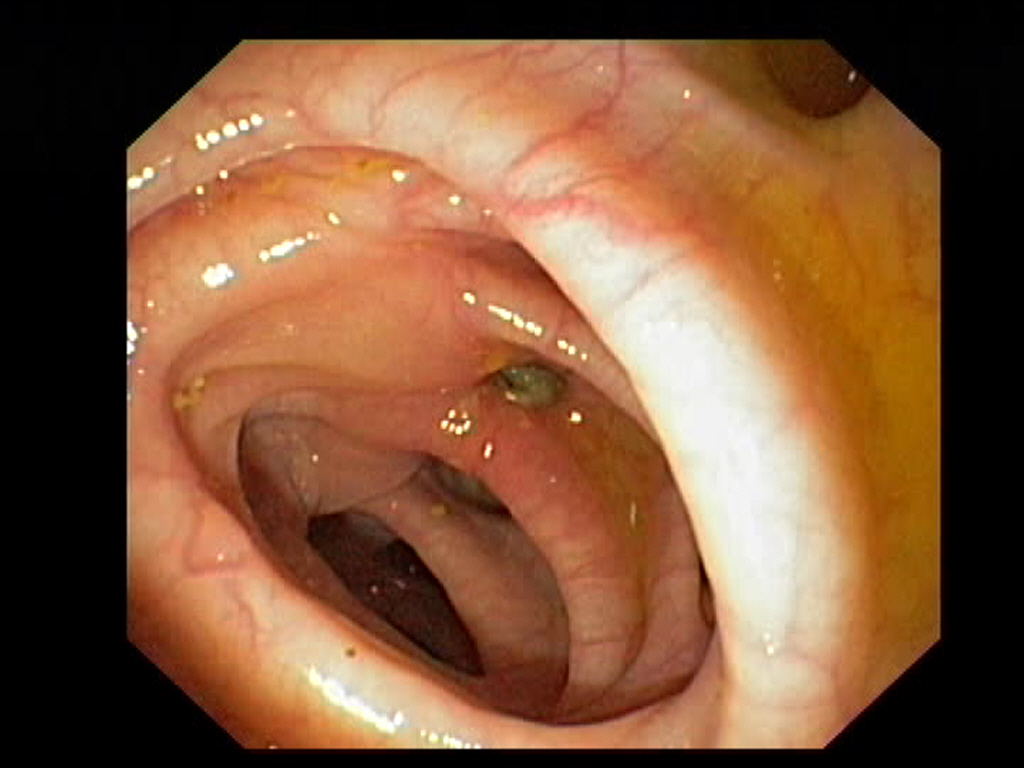

Diverticulosis in the Sigmoid Colon

Diverticulosis in the Sigmoid ColonJust click on a picture!